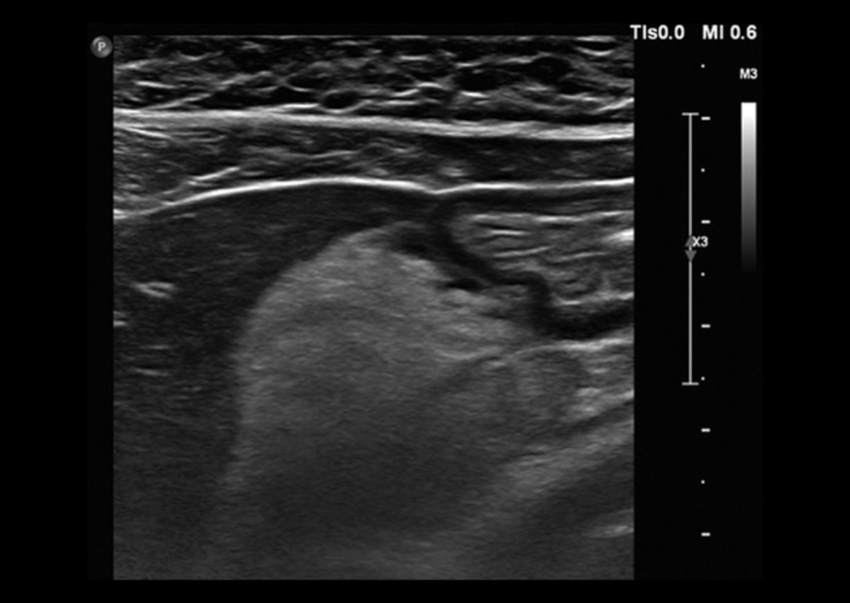

Comunicamos el caso de una mujer de 29 años, sin antecedentes mórbidos de importancia, que consultó por un cuadro de 24 horas de evolución de distensión abdominal y dolor epigástrico, que luego se hizo difuso, sin fiebre. Al examen físico destacaba dolor a la palpación abdominal, preferentemente en el hemiabdomen superior. Se le realizaron exámenes de laboratorio en los que solo se objetivó elevación de la proteína C reactiva con un valor de 14,3 nmol/l. Se decidió estudiar el dolor abdominal con una ecografía, en la que se identificó un área de tejido ecogénico lobulado, relativamente bien delimitado, situado entre el páncreas y la cara posterior del cuerpo y del antro gástrico (Fig. 1), compatible con un proceso inflamatorio del tejido adiposo peripancreático cuya etiología no se precisó. Ante estos hallazgos, se decidió complementar el estudio con una tomografía computada (TC) de abdomen y pelvis con contraste, en la que se confirmó la presencia de un aumento de la densidad del tejido adiposo comprendido entre el páncreas y el estómago, específicamente adyacente a la curvatura menor del estómago y pared posterior (Figs. 2 y 3). El tejido adiposo en relación con la mayor parte de la curvatura mayor presentaba densidad normal. Ante estos hallazgos, se diagnosticó un infarto del epiplón menor, sin signos de complicación, por lo que se decidió manejo con analgesia y controles seriados. La paciente tuvo una evolución favorable con un control a los dos meses con una nueva TC de abdomen y pelvis con contraste, en la que se observó una marcada disminución del aumento de volumen y densidad del omento menor en comparación al examen previo (Fig. 4).

La presentación clínica generalmente es dolor abdominal con sensibilidad y algunas veces con signos de irritación peritoneal. Las pruebas de laboratorio generalmente muestran una elevación leve de los parámetros inflamatorios. El diagnóstico clínico inicial depende de la localización de dolor y generalmente dentro de los diagnósticos diferenciales destacan la apendicitis, la colecistitis y la diverticulitis3,4,5,6. Ecográficamente, la presentación clásica es la de una masa sólida, moderadamente hiperecogénica, no compresible y que se encuentra en íntimo contacto con el lóbulo hepático izquierdo, páncreas y estómago, los cuales no presentan alteraciones. En TC, la presentación es de una masa inflamatoria con densidad adiposa, bien circunscrita, rodeada de órganos normales3,4,5,6,8.